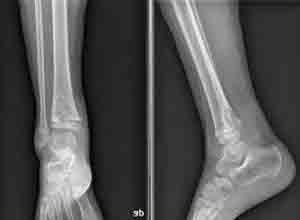

简介长骨骨干结核(tuberculosis of long bone shaft)很少见,其发病顺序为股骨、胫骨、桡尺骨干,肱骨干和腓骨干。10岁以下的儿童最多,且常为多发,30岁以上的则很少见。